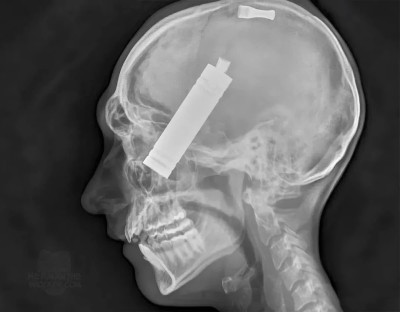

Fig 5: X-ray taken at Medical Examiner's Office showing electronic cigarette mouthpiece and battery housing within decedent's head.

A 38-year-old man was found dead and with burns to 80% of his body inside of his residence. The decedent was found lying on the bedroom floor, with flames partially covering the room.After fire fighters removed him from his residence, he was pronounced dead in the front yard. The decedent had burns covering a large portion of his body, and a wound was present to his face (Fig. 3). Postmortem radiographs revealed the electronic cigarette device was found within the cranium (Fig. 5).

Postmortem examination revealed that the cause of death was due to a traumatic brain injury from the electronic cigarette device exploding. The explosion caused the electronic cigarette,including the mouthpiece and battery housing, to be propelled upward, creating an entrance wound right of the anterior midline in the philtrum region of the upper lip. The cylindrical mouthpiece and battery housing of the electronic cigarette device measured 2 cm by 1 cm and 9.5 cm by 2.5 cm, respectively.The entrance wound was irregularly shaped and measured 1.5 cm from superior to inferior and 0.9 cm from left to right.From the entrance, the two portions of the projectile continued to perforate the full thickness of the maxillary bone, the nasal cavity, nasal septum, nasal concha, ethmoid bone, ethmoid air cells, sphenoid bone, the meninges of the floor of the central portion of the posterior aspect of the anterior cranial fossa of the skull, and the cerebral hemispheres of the brain including the frontal lobes, limbic lobes, the anterior aspects of the basal ganglia, the anterior aspect of the corpus callosum, and the left parietal lobe of the brain. The mouthpiece and larger portion of the projectile traveled roughly 19 cm and 16 cm within the head,respectively. The mouthpiece came to rest within the subdural space overlying the superior-medial aspect of the left parietal lobe of the brain and the larger portion came to rest in the nasal cavity, ethmoid bone, ethmoid air cells, and sphenoid bone (Figs 4 and 5).